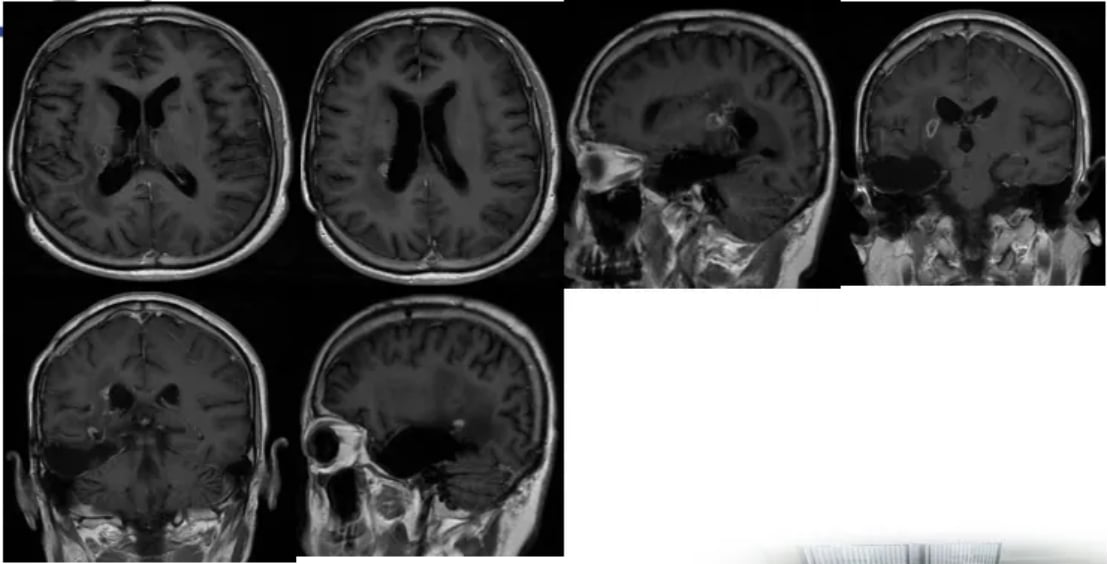

考虑到患者的病情和之前的治疗史,医生决定采用新的治疗策略。自2022年8月起,患者开始接受二线治疗:贝伐珠单抗(800mg)靶向治疗联合替尼泊苷(100mg, d1-3)化疗方案,共进行了8个周期的治疗。

替尼泊苷联合治疗的显著成效

替尼泊苷是一种能够穿透血脑屏障的化疗药物,对脑部肿瘤具有良好的治疗潜力。联合抗血管生成的靶向药物贝伐珠单抗,旨在更有效地控制肿瘤生长。治疗效果在后续的影像学检查中得到了证实。

随访MRI显示,经过联合治疗后,患者脑内病灶的强化程度明显减低,部分病灶甚至消失,病情得到了有效控制。这一积极结果表明,替尼泊苷联合贝伐珠单抗方案在治疗复发性胶质母细胞瘤方面具有显著疗效。

图5 联合治疗期间,病灶强化程度逐渐减低